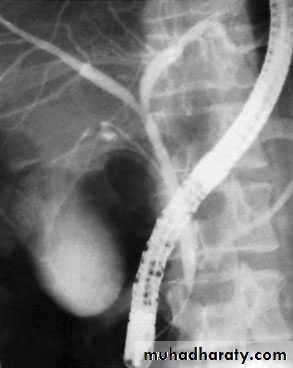

NORMAL ERCP

Endoscopic retrograde cholangiopancreatographydemonstrating stone obstructing the common bile duct (arrow